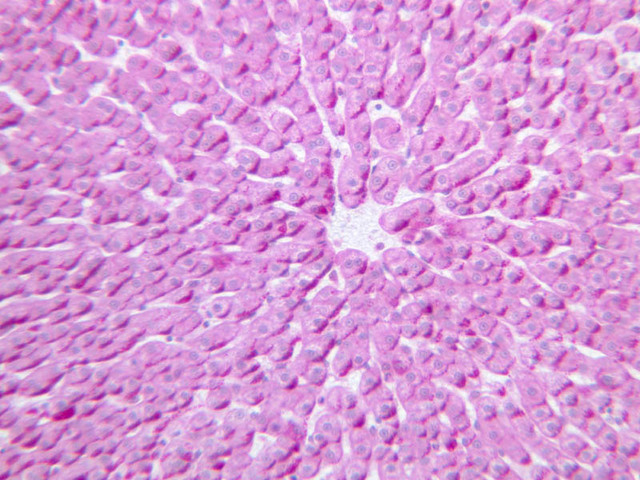

Examine the H&E-stained sections of liver (slides B-29 [10x, 20x, 40x-labeled] [2.5x-labeled, 10x, 20x, 40x] [10x-labeled, 20x, 40x-labeled] and B-30 [2.5x, 10x-labeled, 20x]). At low power, identify the connective tissue capsule (Glisson’s capsule), central veins and portal triads (portal canals). Note that the cells of the liver parenchyma (hepatocytes) appear as cords--more accurately, plates--of cells that radiate out from the central veins and partially enclose blood spaces known as hepatic sinusoids. Note that the plates of hepatocytes appear to branch and fuse and that, as a rule, they are only one or two cells thick. Do you see any binucleate hepatocytes?

Using the high dry objective, study the lining of the central vein and hepatic sinusoids (B-29). In some places the hepatocytes are exposed directly to the sinusoidal lumen, but, as a rule, there is a basal lamina which supports a discontinuous mosaic of endothelial cells and specialized phagocytic cells known as Kupffer cells. Find examples of Kupffer cells and endothelial cell nuclei. Note that in some places you may see a narrow space (the space of Disse) between hepatocytes and the basement membrane underlying endothelial and Kupffer cells. Using the oil immersion (100X) objective, look very carefully along the boundaries between adjacent hepatocytes to see if you can find a bile canaliculus--the most delicate portion of the bile duct system--the walls of which are formed by the plasma membranes of adjacent hepatocytes.

(3) A liver acinus is roughly elliptical in section. Its shorter axis (equator) is defined by the terminal branches of the hepatic artery and portal vein, which course along the boundary between adjacent classic lobules; its longer axis is defined by the two central veins nearest the equator (B-29). Although it is more difficult to visualize a liver acinus than a classic or portal lobule, the concept of acinar organization is very useful because certain features of liver metabolism best fit the acinar model.